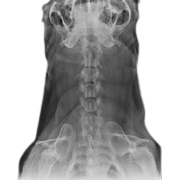

Pet Surgery Center, a nationally leading veterinary surgical team, provides pet orthopedic surgery, spinal and neurological surgery, animal eye surgery, abdominal surgery such as endometritis in dogs and cats, pet sterilization surgery, caesarean section of dogs and cats, cancer and tumor surgery, pet dental services, and state-of-the-art operating rooms, technology and medical equipment.

Operating rooms and equipment in accordance with veterinary navigation standards are as modern as human operating rooms, ready to accommodate cases of referral of sick animals between animal healthcare facilities around the Thonburi area.

Surgical treatment and correction services ensure that your "pet" is as safe as possible when performing surgery with us.